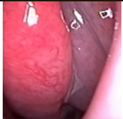

Figure 1. Sample of Nasal Endoscopy indicating Polyp (left) vs Non-Polyp (right)

[6,9] demonstrated the feasibility of a CNN-based system for the automated detection and classification of nasal polyps and inverted papillomas from nasal endoscopic images. The use of endoscopic imaging, akin to colonoscopy in colorectal polyp detection, underscores the adaptability of AI-based diagnostic tools to different medical imaging modalities. The ability of AI to assist clinicians in differentiating between various nasal cavity mass lesions, a task demanding considerable expertise, is particularly promising.